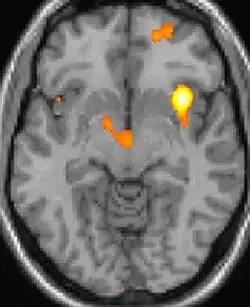

| La tomographie par émission de positons (TEP) montre les zones du cerveau étant activées durant la douleur | ||

Les images par tomographie à émission de positron indiquent les régions du cerveau qui sont activées lors de la douleur, par rapport aux périodes sans douleur. Elles montrent les régions du cerveau qui sont toujours actives durant la douleur en jaune/orange (appelé "matrice-douleur"). La zone au centre (dans les trois vues) est spécifiquement activée uniquement pendant la crise. Les photos sur la ligne du bas (effectuées par VBM) montrent les différences structurelles entre les patients souffrant d'AVF et des personnes saines : seulement une partie de l'hypothalamus est différente[50],[51].